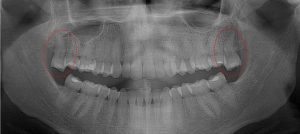

This 21 year old patient has all four 3rd molars present (circled). The roots are approximately 2/3rds formed. The lower right 3rd molar cannot erupt any further; it is distally tipped into the ramus of the mandible. The lower left 3rd molar likely will not erupt any further; it is pushing into the undercut of the distal of the 2nd molar.